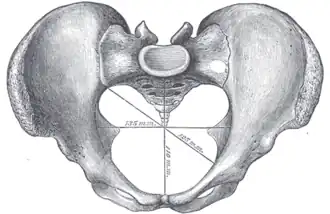

Alternatively, the pelvis is divided into three planes: the inlet, midplane, and outlet.[4]

Additional images

Diameters of pelvic inlet